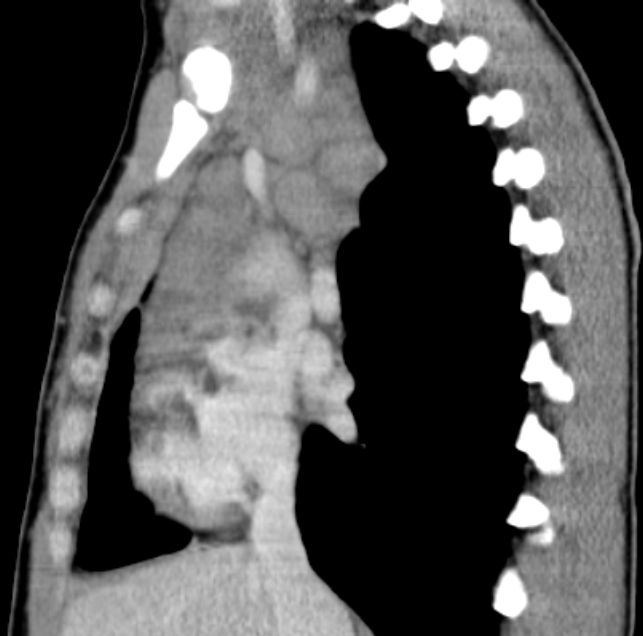

| thorakal | 21-jährige Frau mit Morbus Hodgkin mediastinal und zervikal beiderseits. Stadium IIA, Risikofaktor: hohe BSG. Noduläre Sklerose. | ||